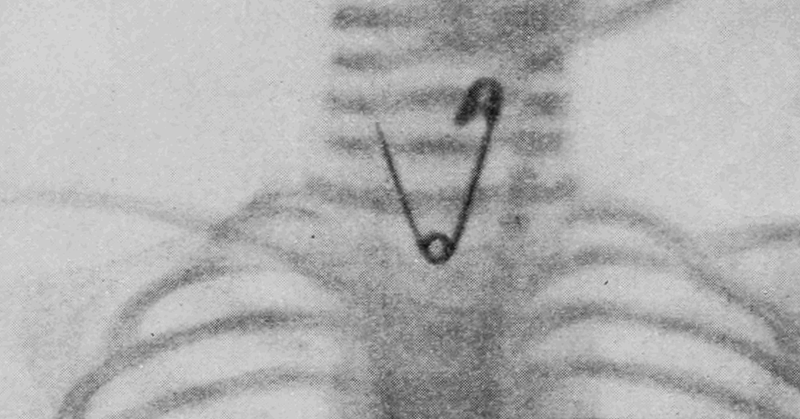

De agulhas a projéteis: a tecnologia que encontra metais perdidos no corpo // apoio do CNPq:

theconversation.com

Brasileiros desenvolvem técnica precisa e acessível para localizar objetos metálicos no corpo, tornando cirurgias de remoção mais rápidas e eficazes